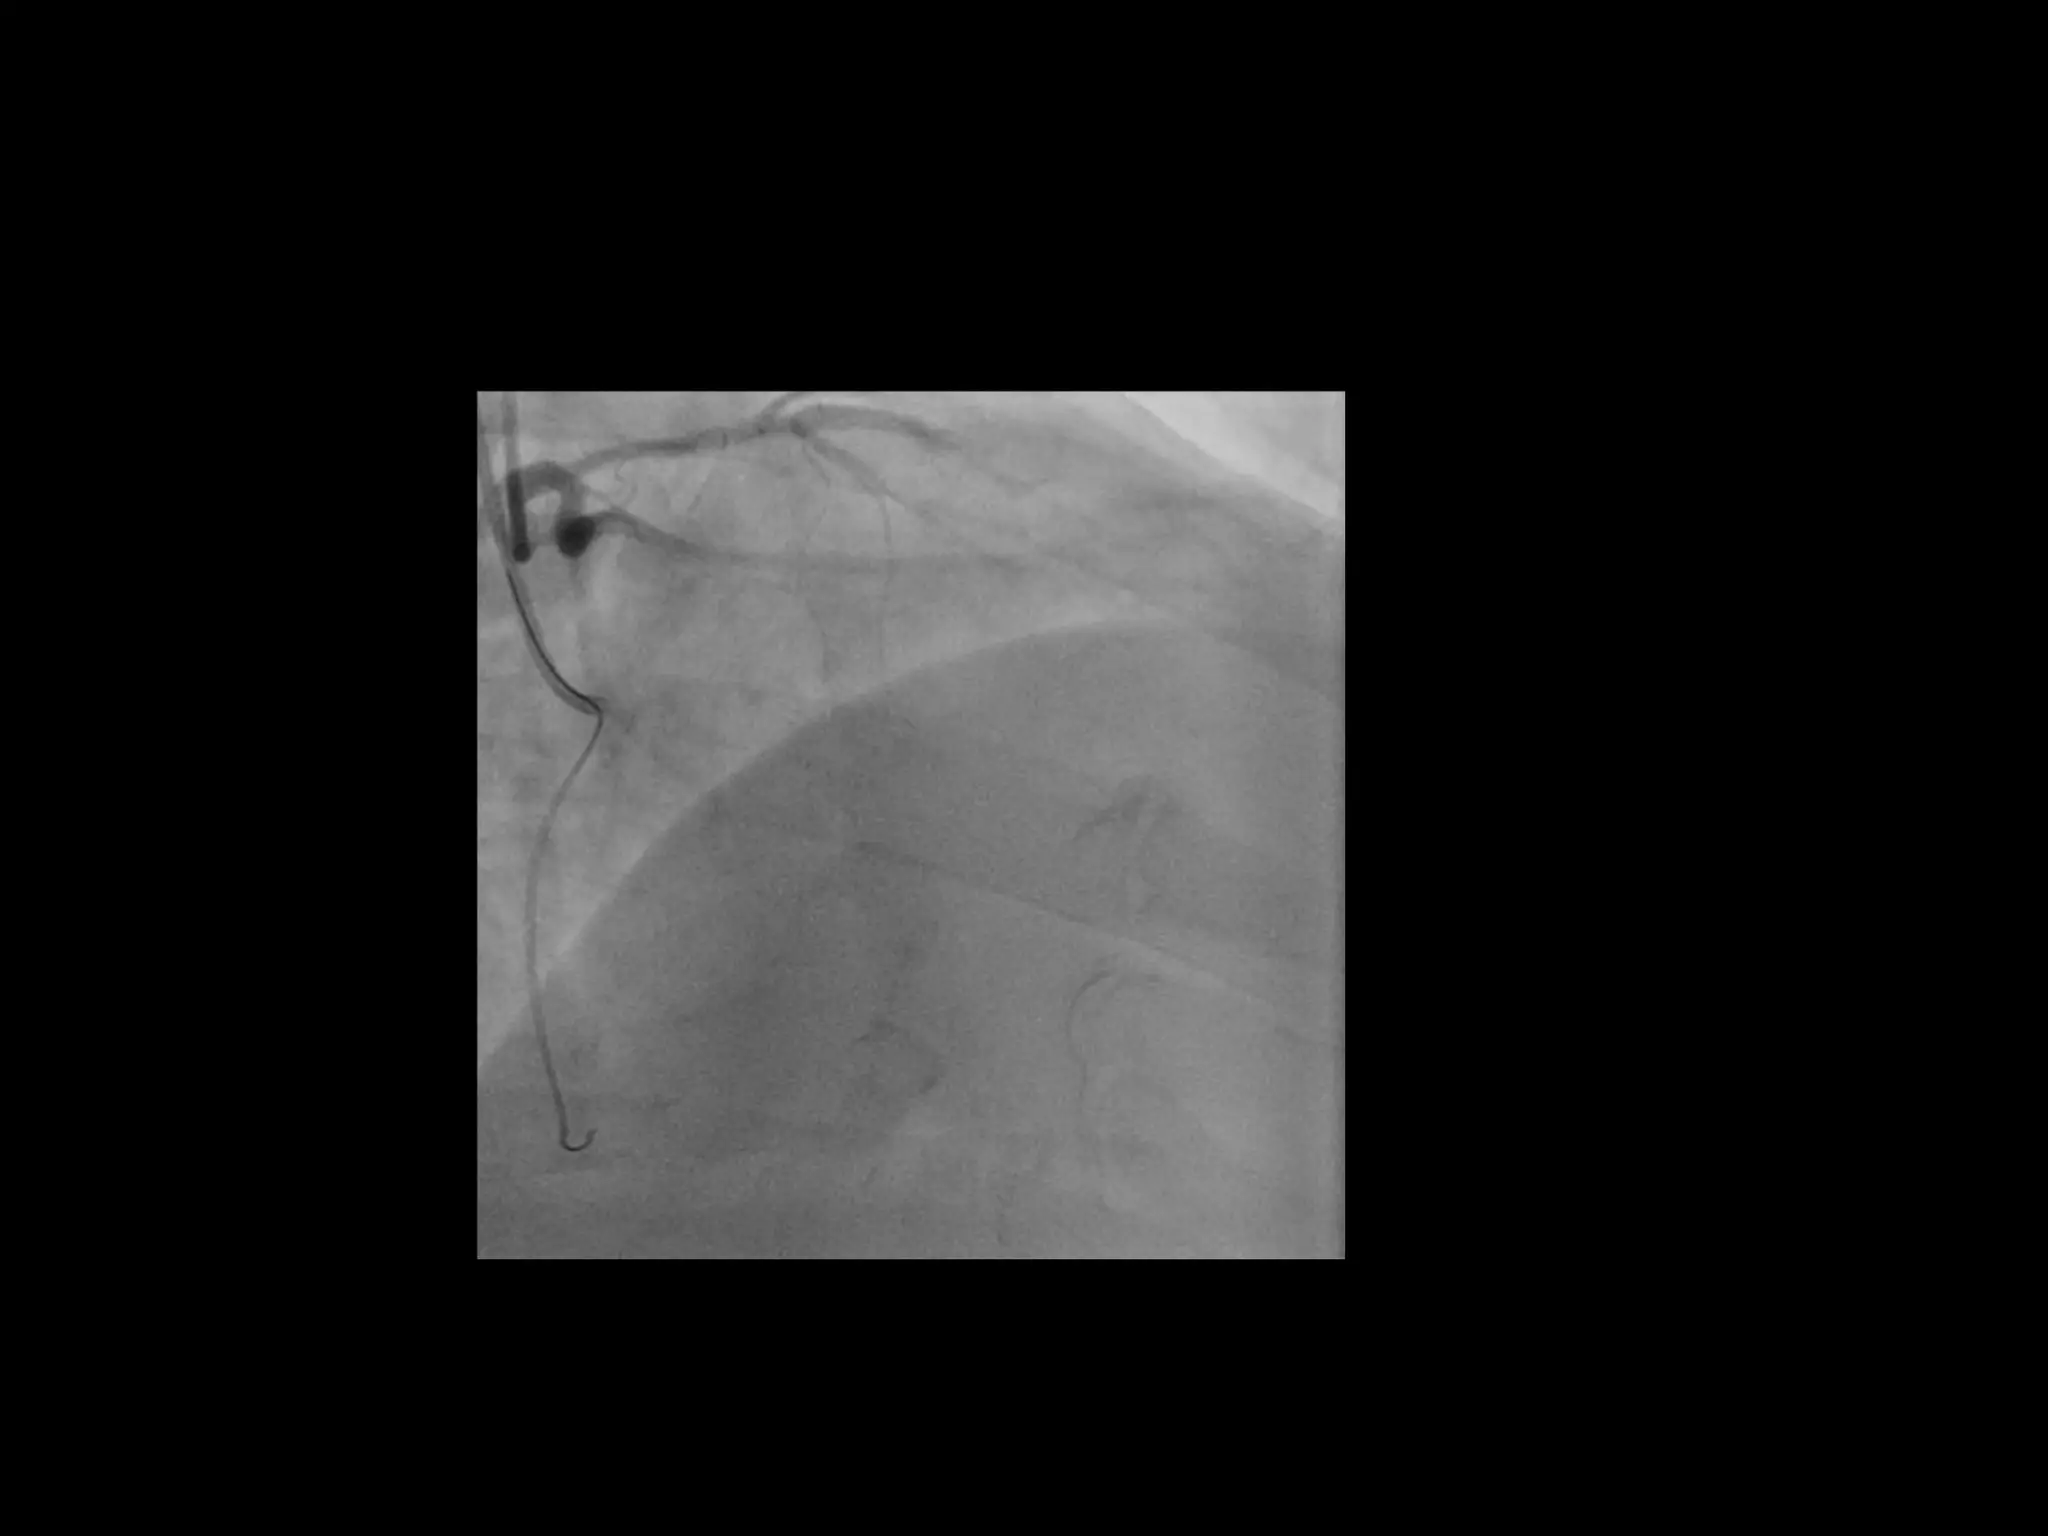

This document provides guidance on evaluating the feasibility of percutaneous coronary intervention (PCI) for a chronic total occlusion (CTO). Key factors to consider include: the patient's tolerance for a long procedure, contrast load, and radiation exposure; the CTO's proximal cap ambiguity, length, distal landing zone, and presence of interventional collaterals; and ensuring good quality angiography. With adequate planning and use of appropriate CTO techniques, feasibility is nearly always present for symptomatic patients. Success rates of CTO-PCI are reported to be 94% when using a planned approach.